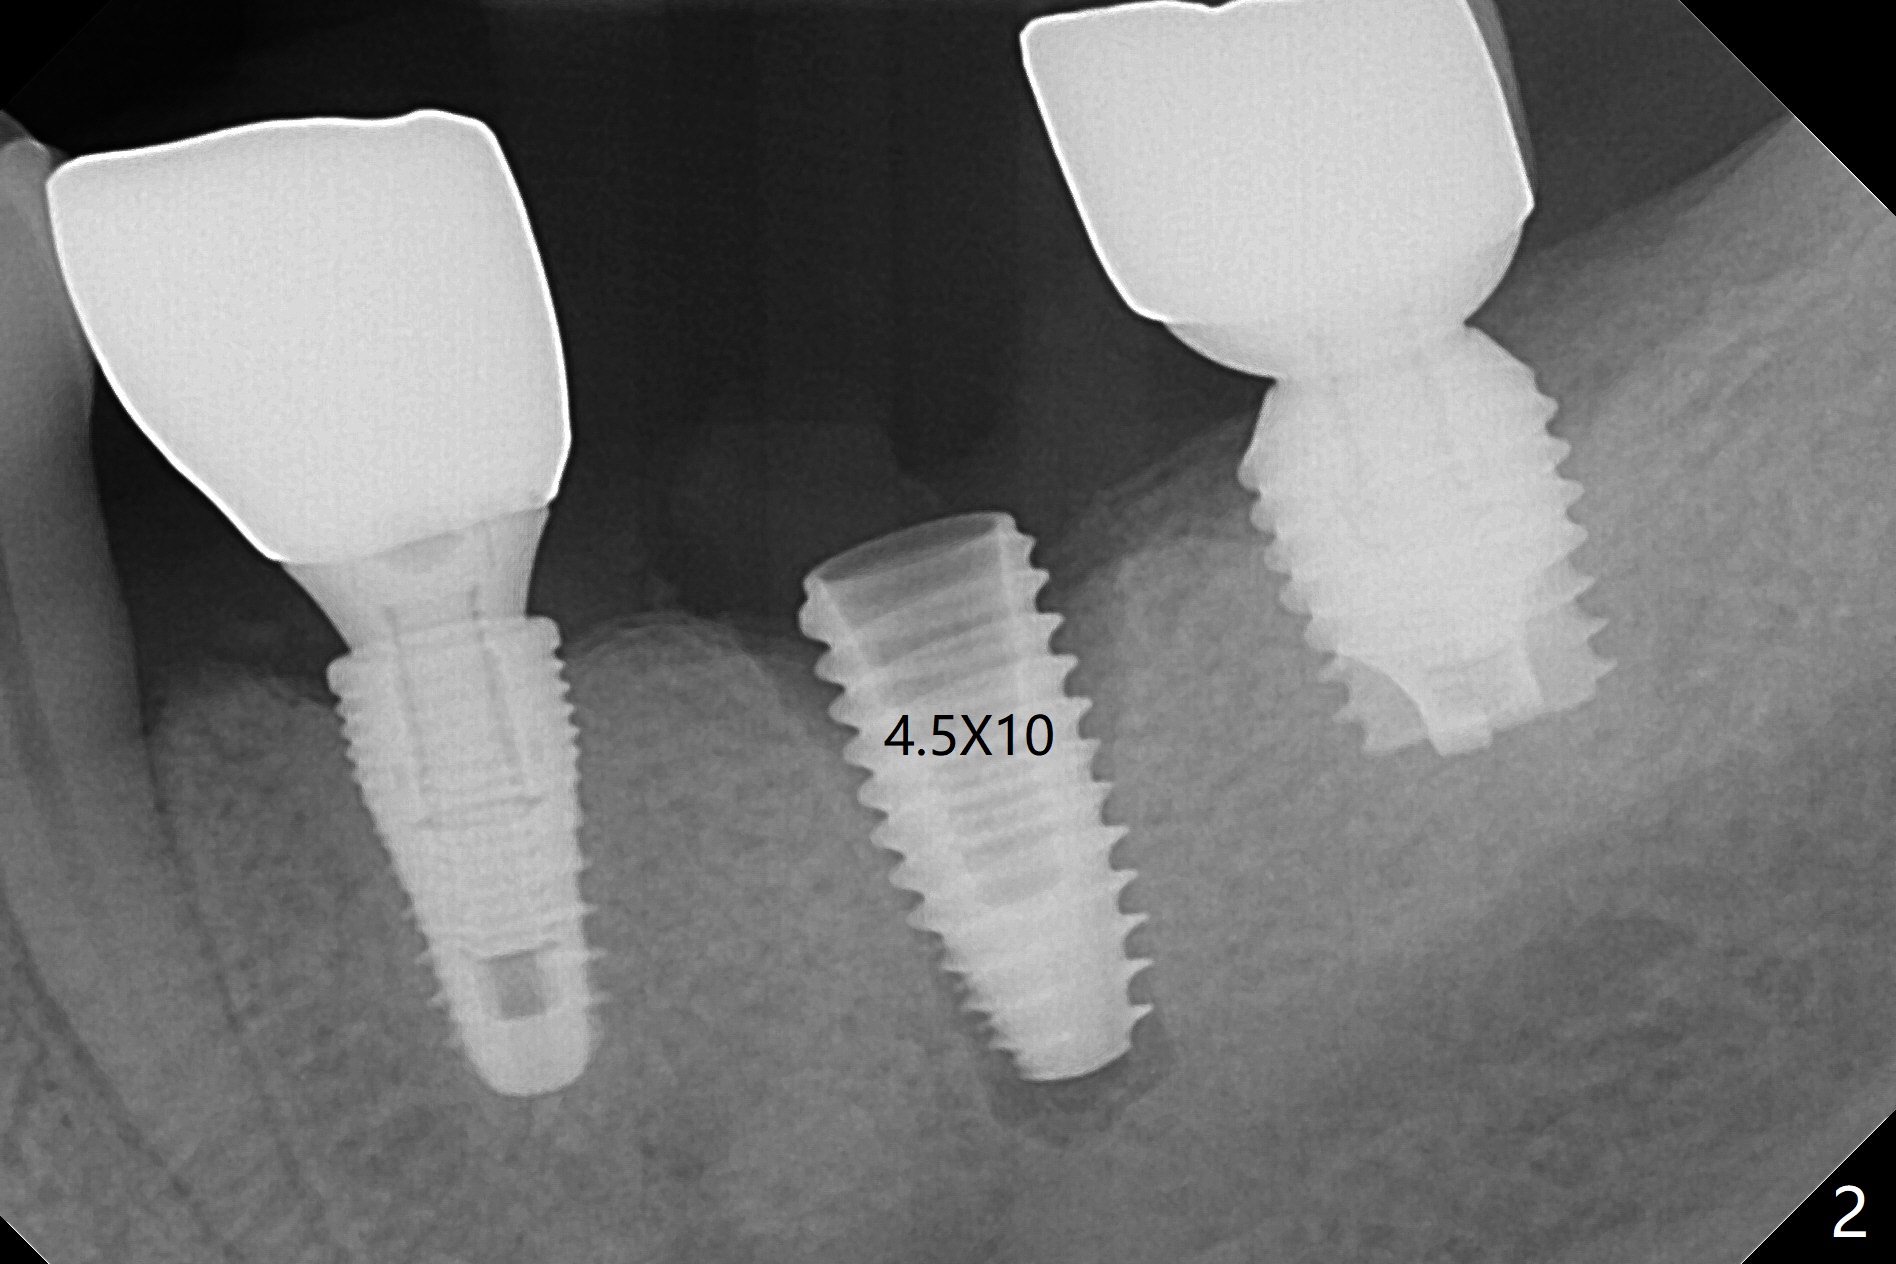

Since there is ~ 2 mm bone apical to the 5x8 mm loose implant at #19 (Fig.1), primary stability is achieved for a 4.5x10 mm dummy IS implant (having better surface treatment than the previous implant) when osteotomy is finished with a 4 mm drill (Fig.2). It is the same associated with a 4.5x7.3 mm definitive one with apical space (Fig.3 *). After depth adjustment to make sure that the implant is subcrestal circumferentially, sticky bone is placed on the top of the implant and around the implant at #18 (Fig.4 *), followed by PRF membranes and suturing with 5-0 PGA and 4-0 Chromic gut suture. Periodontal dressing is applied around the cemented abutment at #18 for additional retention. There is no paresthesia postop. In fact immediate implant redo is fairly safe. The wound heals 1 month postop (Fig.5). There is reorganized bone coronal to the healing screw 4 months postop (Fig.6), which is confirmed in uncovering. One month post uncover, the 6x4 mm healing abutment is found to be loose, suggesting incomplete seating after uncover. A 5.2x4.5(4) mm cemented abutment seems to be incompletely seated (Fig.7). It remains the same after 5.5 and 6.0 mm profile drills (Fig.8,9). A 4.5x4.5(4) mm abutment appears to be completely seated (Fig.10). When the crowns of #18 and 19 are cemented, the gingival embrasure between them is narrow (Fig.11 ^) because of bulky porcelain build-up (*). The tooth #21 with buccal Class V defect (Fig.12 *) seems to have occlusal trauma 1 year 6 months post cementation of #18 and 19. The problems are subsequently taken care of.